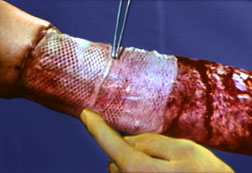

Staples

Staples are less reactive than the least reactive suture. Deeply implanted staples do not affect tissue defenses, although staple cross members that are flush with the skin can produce cross-hatched scarring. The development of disposable staplers with absorbable tacks obviates the need for removal of staples. Subcuticular closure of skin is now also possible through the use of a disposable stapler that uses twin gripper blades to approximate and evert the wound edges and insert a disposable pin into the dermis